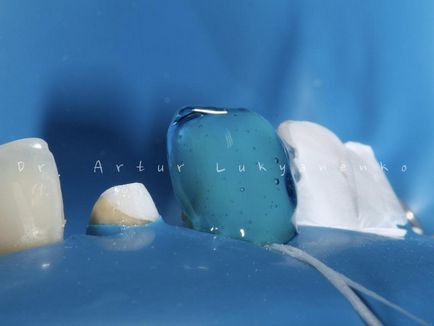

Photo 10. Land nyomásmentesítés régi tömések ismét helyreállt folyékony kompozit átlátszó színes gumi gát elszigetelten.

Photo 10. Land nyomásmentesítés régi tömések ismét helyreállt folyékony kompozit átlátszó színes gumi gát elszigetelten.